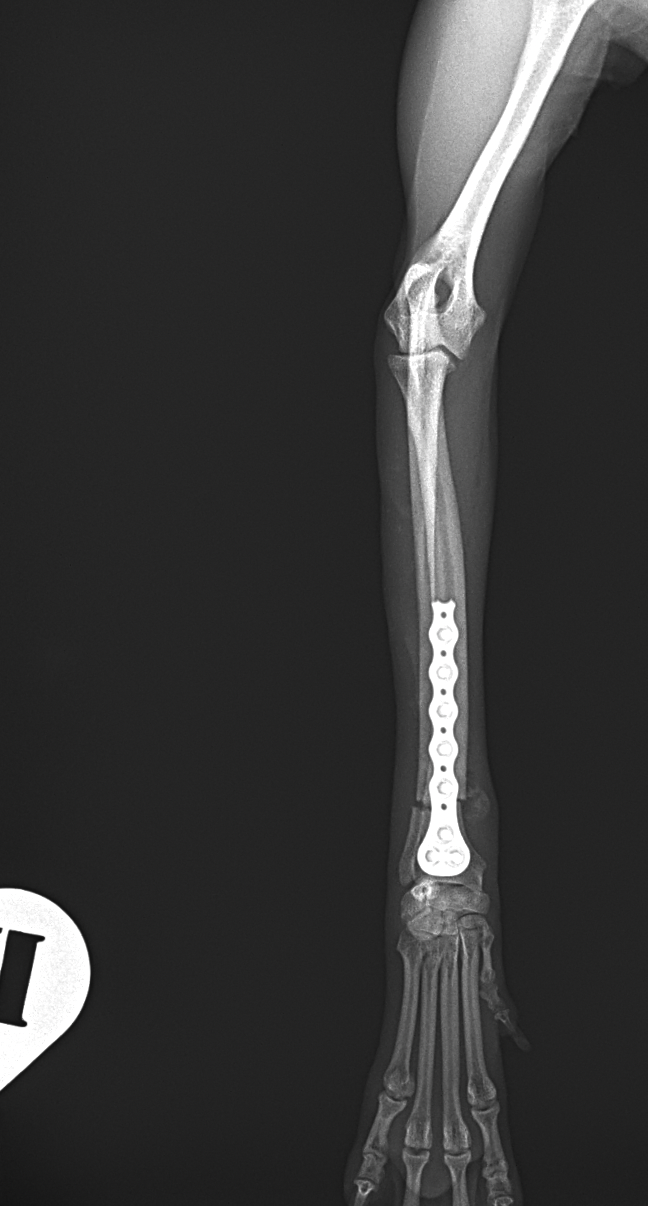

橈骨固定術 #270 極小犬(1.4kg)の橈骨固定術依頼です。骨幅3.8mmに対して1.2 Titanium Locking Plateと自家海綿骨移植を実施しています。初期固定強度を担保するために、外固定を併用しながらしばらくは安静が必要です。 症例カテゴリー 放射線治療整形外科軟部組織外科脳神経外科内科腫瘍外科救急・集中治療リハビリテーション科腫瘍内科内視鏡科脳神経科呼吸器外科中医・漢方猫の腎移植循環器科